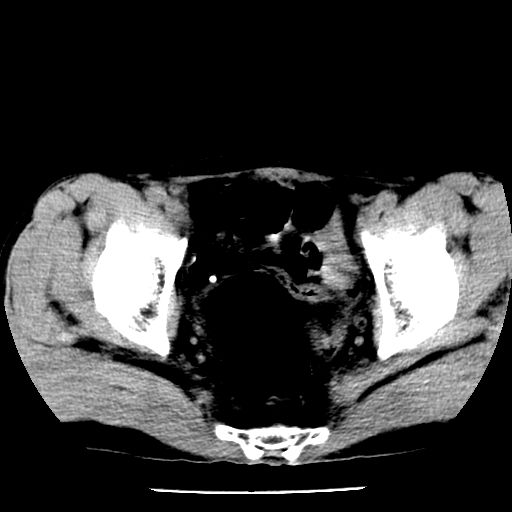

男,59岁,“结核性胸膜炎”30余年,胸部经常疼痛,多次x检查提示“肺部”炎症。腹部疼痛5日,b超提示:“肝内短管结石,余显示不清,建议进一步检查。”

两肺结核并右侧胸腔积液;脾脏、腹腔及腹膜后淋巴结结核[陈旧性];肝内胆管结石

胸部腹部都是结核(双肺。纵隔淋巴结,肝脏,脾脏,肠系膜)

两肺结核并右侧胸腔积液;脾脏、腹腔及腹膜后淋巴结结核[陈旧性];肝内胆管结石。直肠息肉?